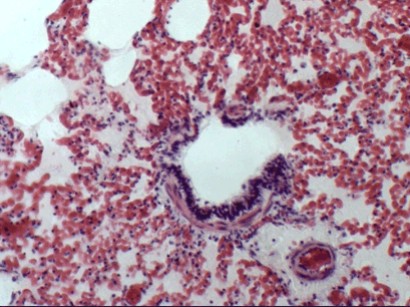

Препарат: Острая застойная гиперемия и отек леких

При застойной гиперемии легких расширяются и переполняются кровью капилляры перегородок и вен междольковой соединительной ткани. Рассматривая гистологический препарат уже при слабом увеличении микроскопа можно видеть, что строение легкого сильно изменено. Просветы альвеол и бронхиол частично или целиком заполнены розоватой или серо-розоватой пленкой,  а кровеносные сосуды (вены и респираторные капилляры) сильно налиты кровью. Для более детального изучения необходимо найти такой участок препарата, где альвеолярное строение легочной ткани заметно наиболее отчетливо. При большом увеличении здесь видны неравномерно расширенные капилляры, которые местами четкообразно вдаются в просвет альвеол и придают альвеолярным перегородкам утолщенный вид. Если в печени,  вследствие компактности органа, скопления отечной жидкости (трассудата) нет,  то в легком эта жидкость в большом количестве обнаруживается в полостях - альвеолах. Трассудат,  или вернее белок транссудата, оставшийся после обезвоживания препарата спиртом,  заметен в альвеолах либо в виде мельчайшей зернистости,  заполняющей просветы альвеол целиком или частично. В последнем случае пленочка транссудата содержит воздух в виде неокрашенных, различной величины ячеек. Некоторые альвеолы почти целиком заполнены воздухом,  в транссудат только узкой полоской располагается около альвеолярных перегородок, клеточных элементов в транссудате мало.

Обычно в нем находят немного эритроцитов, единичные лимфоциты,  нейтрофильные лейкоциты и слущенные клетки альвеолярного эпителия.  Дифференцировать отдельные клетки следует, в основном, по ядрам, так как протоплазма окрашивается в один цвет с транссудатом и не имеет с ним резких границ. Ядра слущенных эпителиальных клеток выделяются крупной величиной, бледной окраской и округло-овальной или пузырьковидной формой.

Рис.78.Отек и гиперемия легких:

1.	Расширение и переполнение кровью капилляров альвеол и альвеолярных перегородок;

2.	Просветы альвеол заполнены серо-розовой пленкой (отек легочных альвеол).

Эти клетки в сравнении с клетками крови значительно больше.

Одновременно с этим отеку может подвергаться соединительная ткань около кровеносных сосудов, бронхов и между дольками, что вы-зывает там набухание и утолщение коллагеновых волокон.